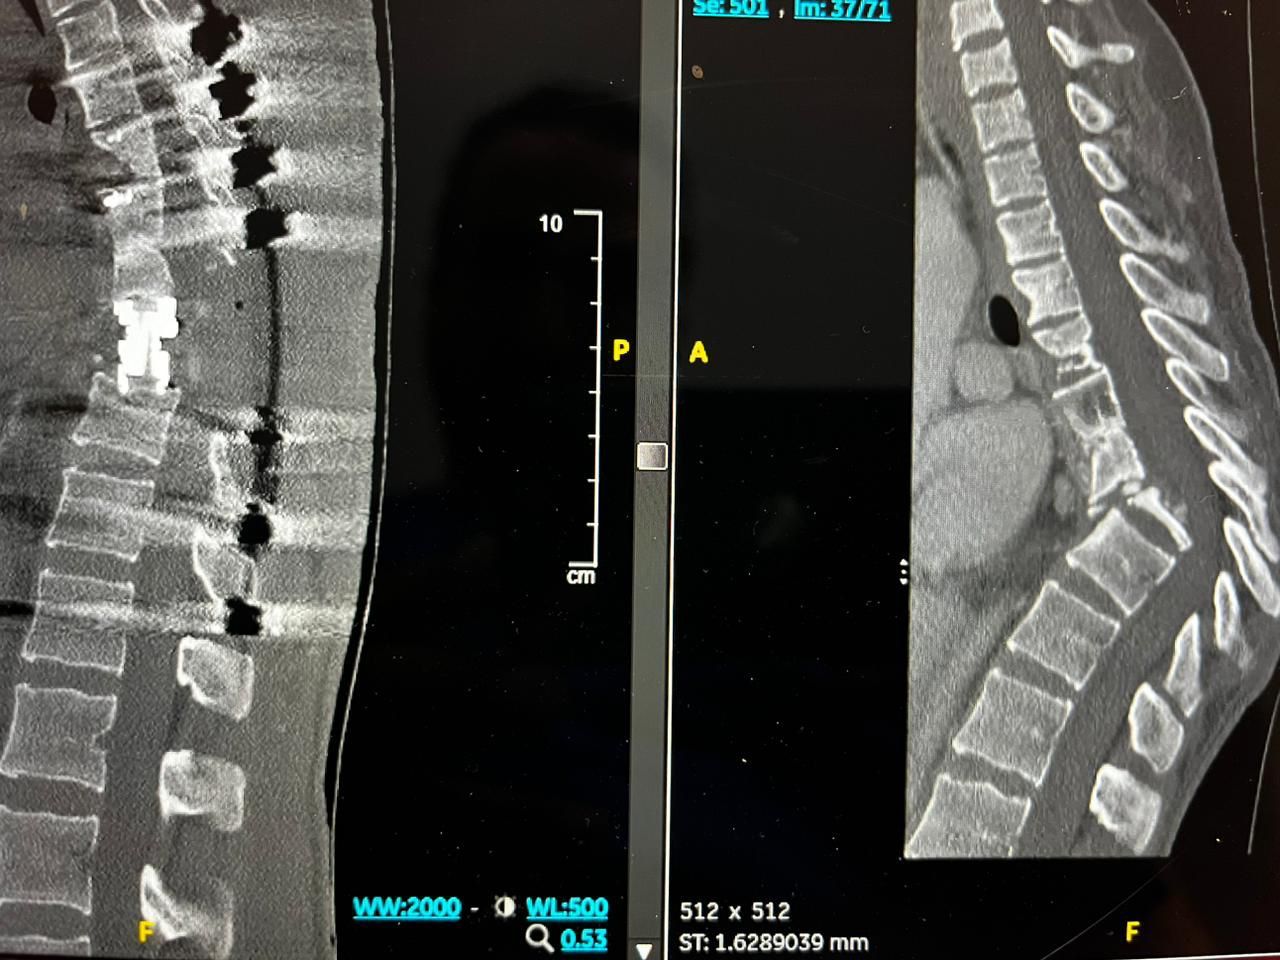

وكانت المريضة التي تبلغ من العمر ٢٧ عامًا ، تعاني من مرض الذئبة الحمراء وهشاشة العظام ومصابة بداء الدرن في العمود الفقري، وفور وصولها إلى مدينة الملك فهد الطبية، أجريت لها الفحوصات الطبية والتي أظهرت وجود سوائل في العمود الفقري، بسبب تدهور حالتها الصحية، وتهتك في العمود الفقري وتشوه معقد يتكون من تحدب وتزحزح للفقرات الصدرية وضغط على الحبل الشوكي في مكان التشوه.

وعلى الوقت ذاته، خضعت المريضة في بداية مرحلة العلاج إلى سحب السوائل من العمود الفقري وعلاج الدرن، وهشاشة العظام الأمر الذي سهل من مراحل الخطة العلاجية، الأمر الذي جعل الفريق الطبي يؤكد على قراره في إجراء العملية والتي استمرت 12 ساعة متواصلة تمكنوا خلالها من فتح الظهر وزراعة وسائل التثبيت، حيث تلاها بعدة أيام قص العظام الخلفية والأمامية للعمود الفقري ووضع دعامة لتصحيح العمود الفقري للشكل الطبيعي مع المحافظة على سلامة الحبل الشوكي.